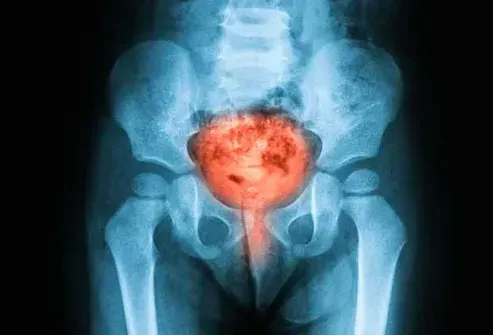

Tumore

Sia i tumori cancerosi che quelli benigni possono farti fare pipì di più perché occupano più spazio dentro o intorno alla vescica. Il sangue nelle urine è il segno più importante se è il cancro. Parla con il tuo medico se vedi il sangue notare un nodulo nella pancia inferiore o scoprire che fa male fare pipì.